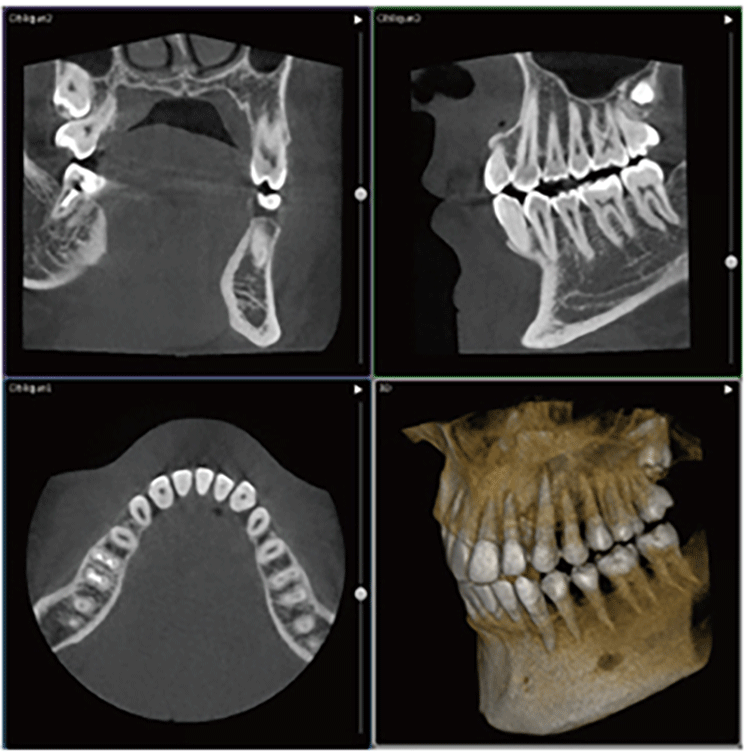

精密な検査と診断

治療を成功させるためには、正しい診断と治療計画はとても大切です。

問診、口腔内検査、レントゲン検査、そしてCT検査など、検査も丁寧にしっかりと行います。